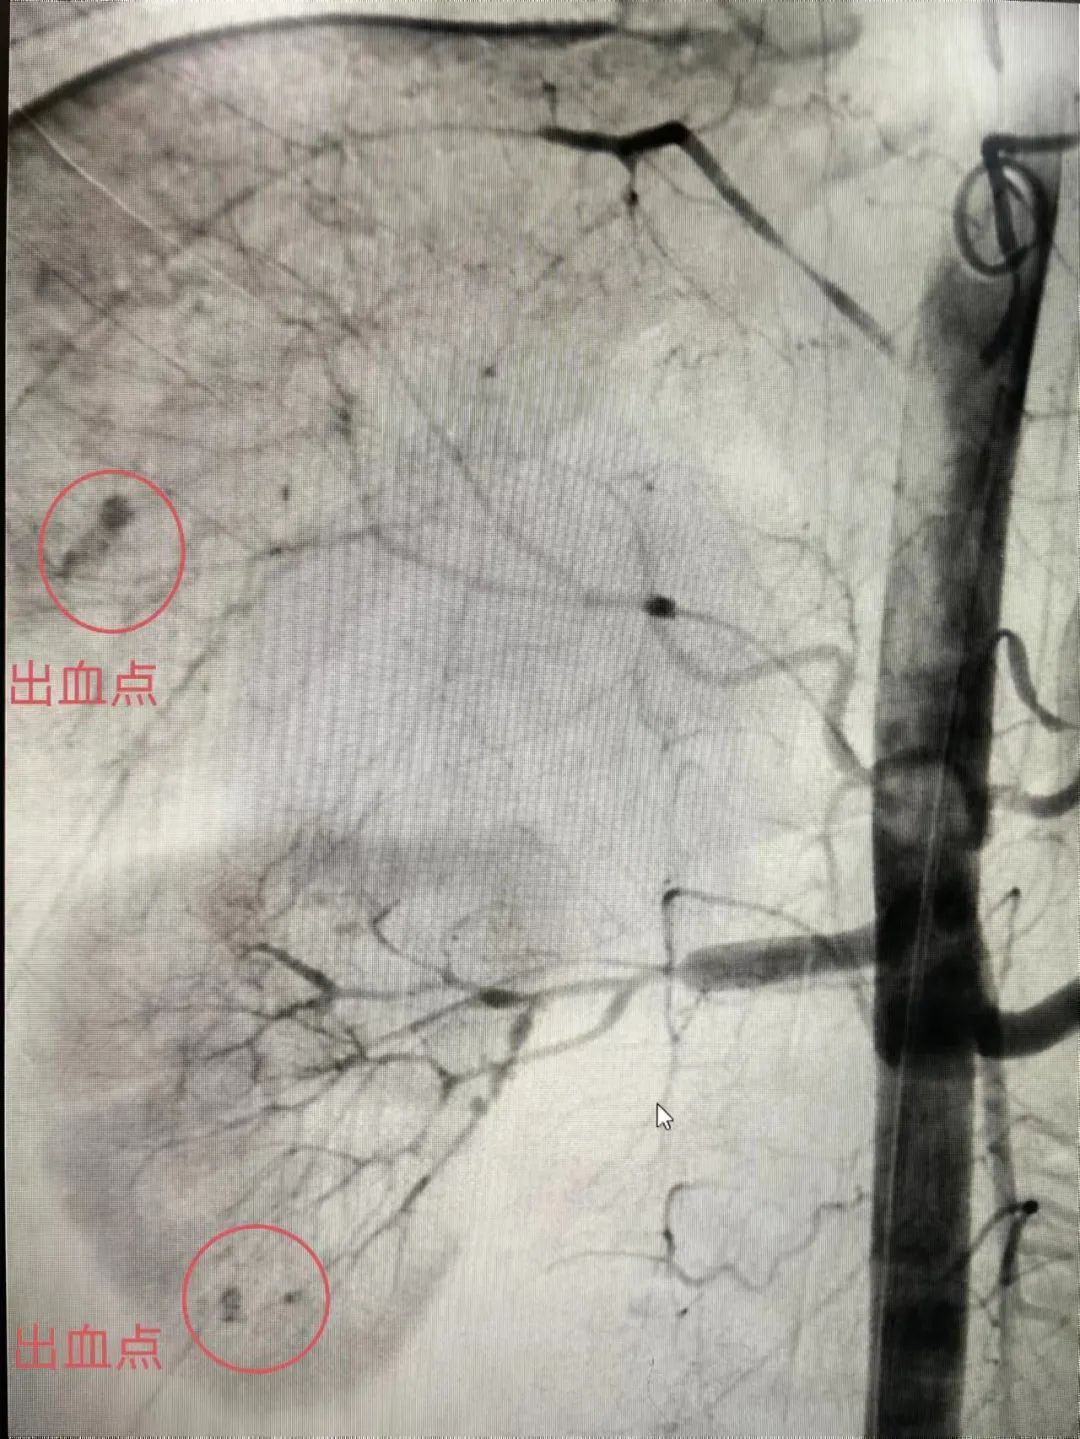

术中,市中医医院手术团队通过腹腔镜探查小伟腹腔脏器损伤情况,明确出血部位、出血点,吸净腹、盆腔内血液及血块,对肝挫裂伤创口行缝扎止血,手术顺利,术中肝脏无活动性出血;同时探查腹腔发现后腹膜血肿范围较前扩大,考虑右肾挫伤严重伴有活动性出血,紧急将小伟转送至介入导管室行腹主动脉、肝动脉、肾动脉、脾动脉、髂动脉造影检查。外周血管介入手术团队经反复造影明确后,对肝右分支、右肾分支及右股深分支的出血动脉进行栓塞止血处理,栓塞后复查造影均提示出血动脉截断。小伟急性出血量共约2500ml至3000ml,术中补充输血2000ml左右,手术过程顺利,经过这场从黑夜到黎明的较量,止血成功,小伟暂时脱离了生命危险!

△术中造影显示肝脏、右肾、右股深分支出血点